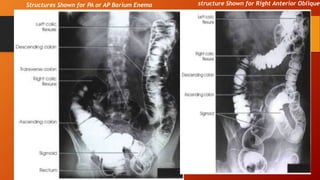

structure Shown for Right Anterior ObliqueStructures Shown for PA or AP Barium Enema

structure Shown forRight Anterior ObliqueStructures Shown for PA or AP Barium Enema